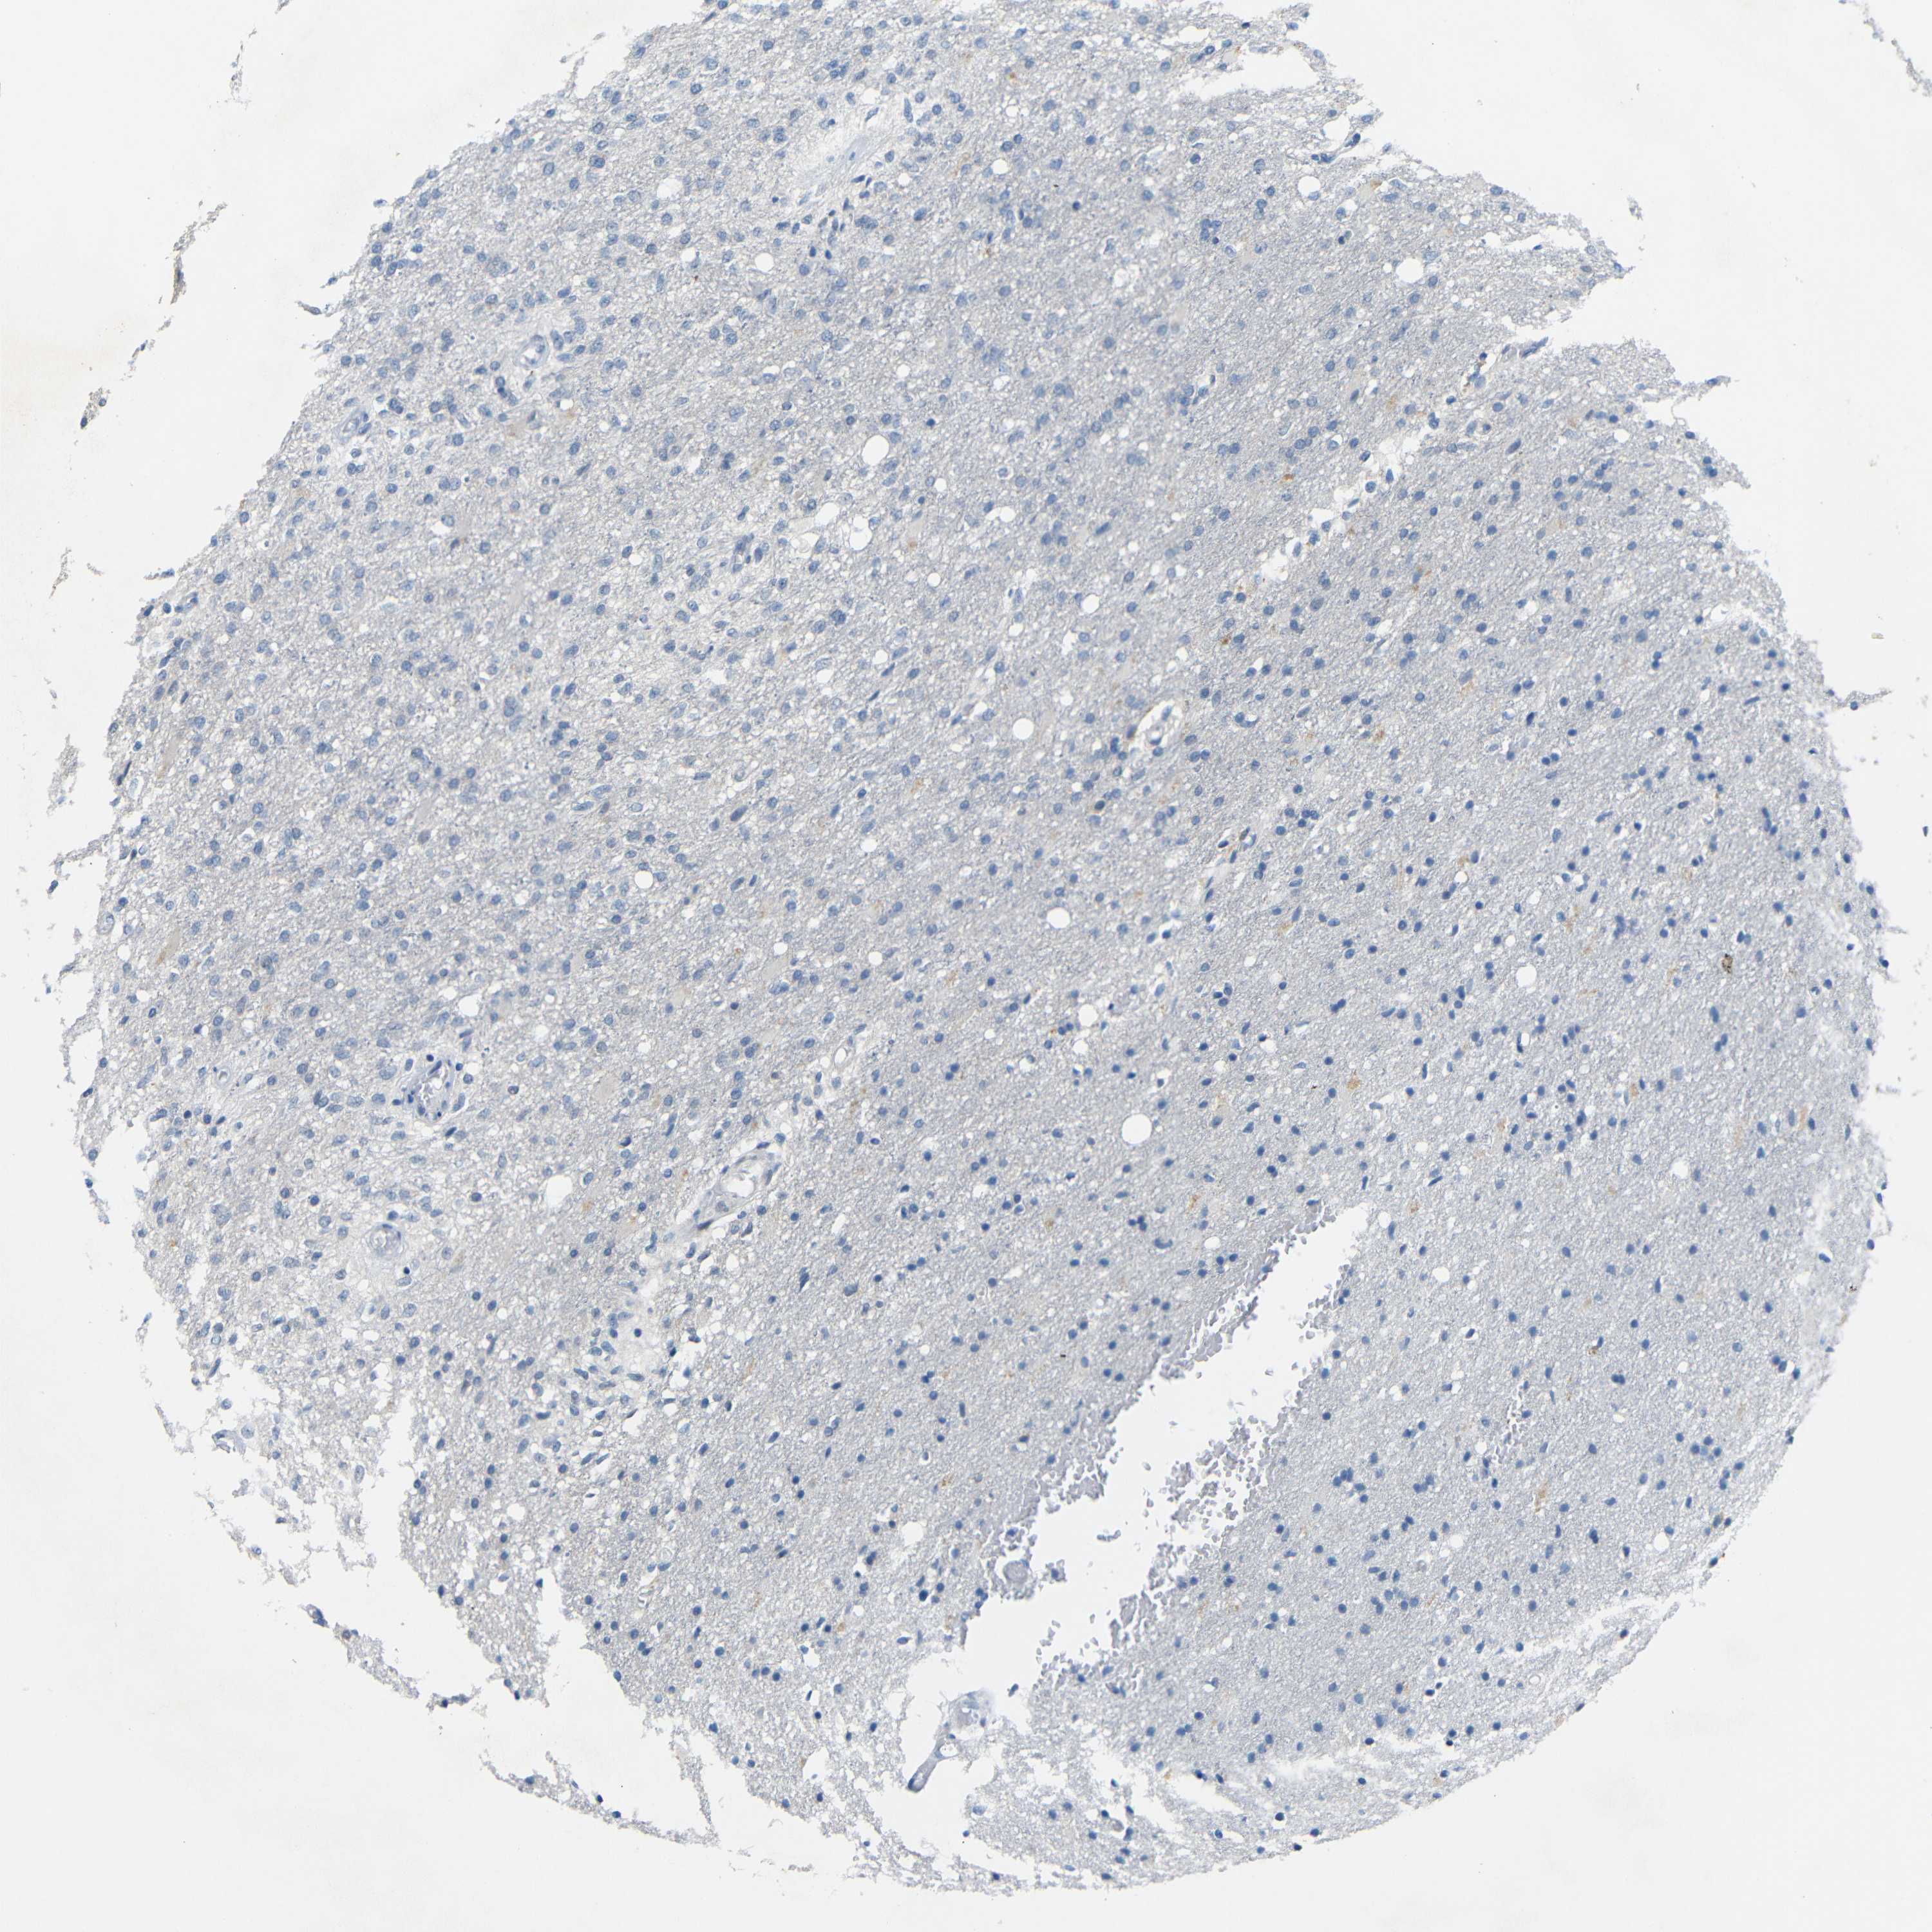

GLIOMA - Protein expressioni

A mouse-over function shows sample information and annotation data. Click on an image to view it in a full screen mode. Samples can be filtered based on level of antibody staining by selecting one or several of the following categories: high, medium, low and not detected. The assay and annotation is described here.

Note that samples used for immunohistochemistry by the Human Protein Atlas do not correspond to samples in the TCGA dataset.

Antibody stainingi

Antibody staining in the annotated cell types in the current human tissue is reported as not detected, low, medium, or high, based on conventional immunohistochemistry profiling in selected tissues. This score is based on the combination of the staining intensity and fraction of stained cells.

Each image is clickable and will lead to virtual microscopy that enables deeper exploration of all samples and also displays staining intensity scores, fraction scores and subcellular localization as well as patient and tissue information for each sample.

Antibody HPA013185

Staining

High

Medium

Low

Not detected

Intensity

Strong

Moderate

Weak

Negative

Quantity

>75%

75%-25%

<25%

None

Location

Nuclear

Cytoplasmic/membranous

Cytoplasmic/membranous,nuclear

Glioma, malignant, High grade

Glioma, malignant, Low grade